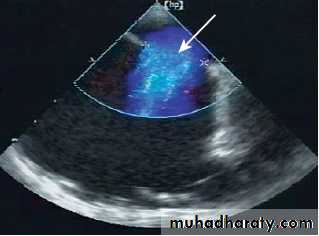

Blood cultureEchocardiography

Echo :- shows the defect , RV and PA dilatationTEE